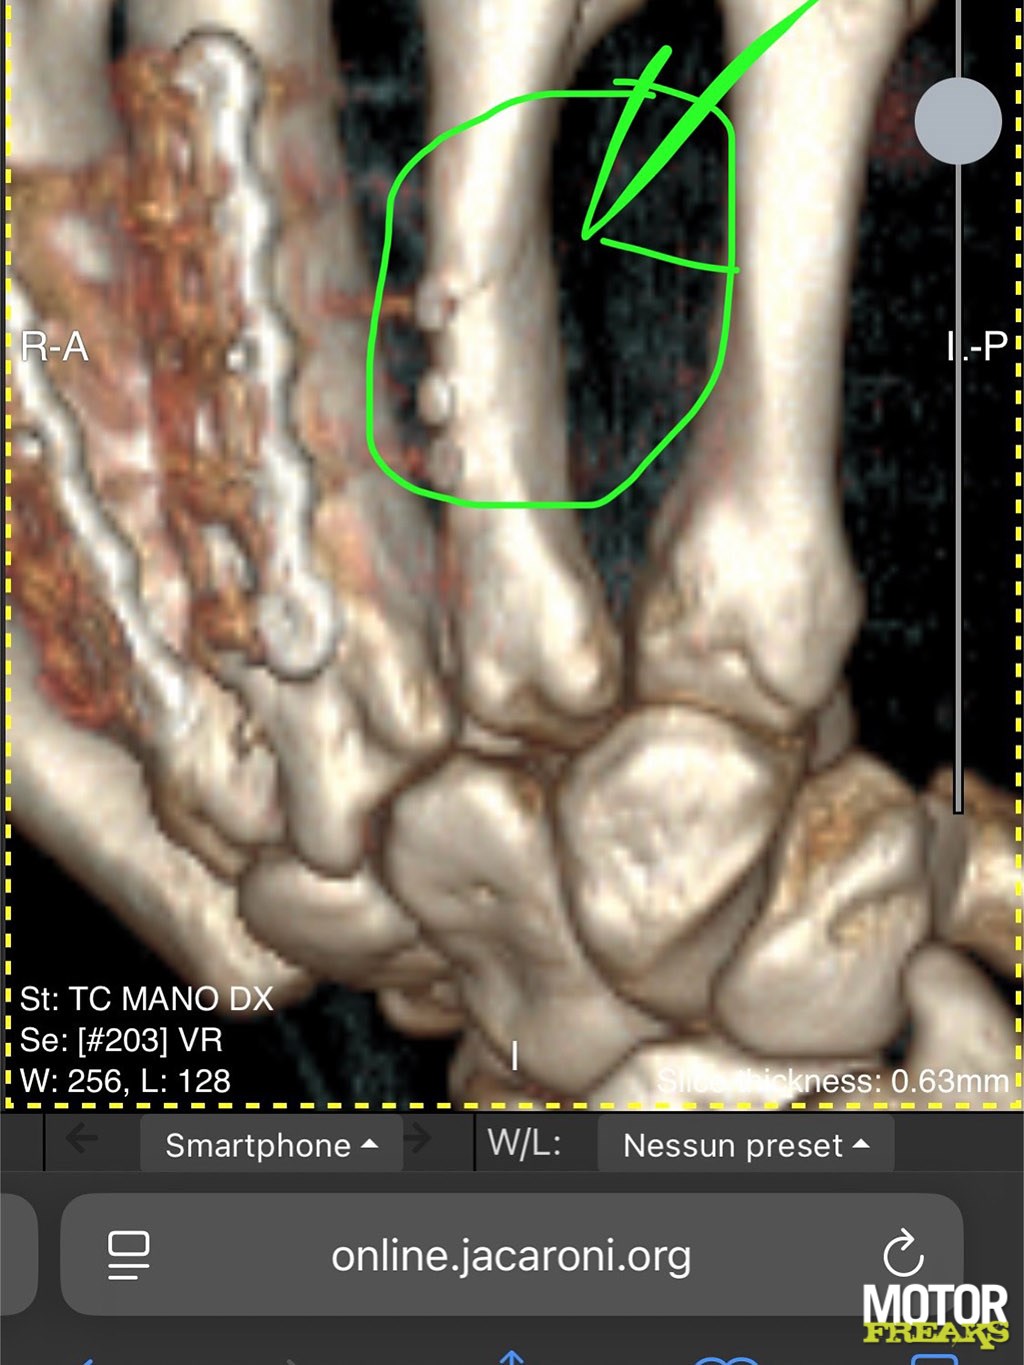

Afgelopen vrijdag was Petrucci aan het trainen met een elastiek toen hij met zijn rechterhand tegen een muur stootte. Op die hand zitten al 20 schroeven en 2 platen in drie middenhandsbeentjes, en daarbij is nu ook het vierde middenhandsbeentje, waarin hij drie schroeven heeft, gebroken.